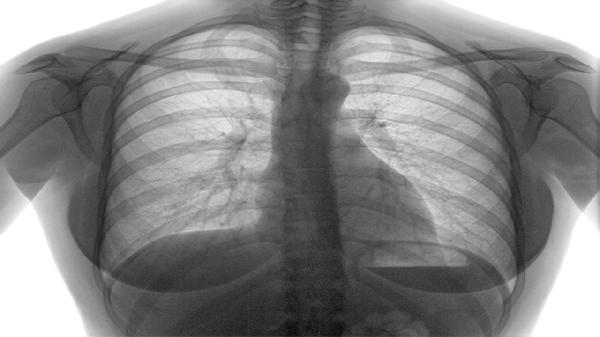

肺部玻璃结节通常是指肺部磨玻璃结节,属于肺部影像学表现,可能是炎症、感染或早期肺癌等疾病引起。肺部磨玻璃结节主要有炎性病变、肺结核、肺真菌感染、肺腺癌、肺转移瘤等类型。

发现肺部磨玻璃结节后应避免过度紧张,多数情况下属于良性病变。建议遵医嘱定期复查胸部CT,观察结节大小、形态变化。日常生活中应戒烟限酒,保持室内空气流通,适当进行有氧运动增强肺功能。如出现持续咳嗽、胸痛、咯血等症状应及时就医。饮食上可多摄入富含优质蛋白和维生素的食物,如鸡蛋、牛奶、新鲜蔬菜水果等,有助于增强免疫力。